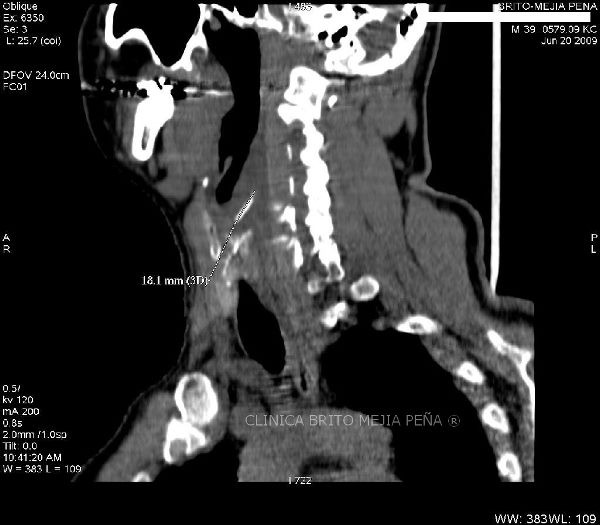

Espina en espacio retrofaríngeo